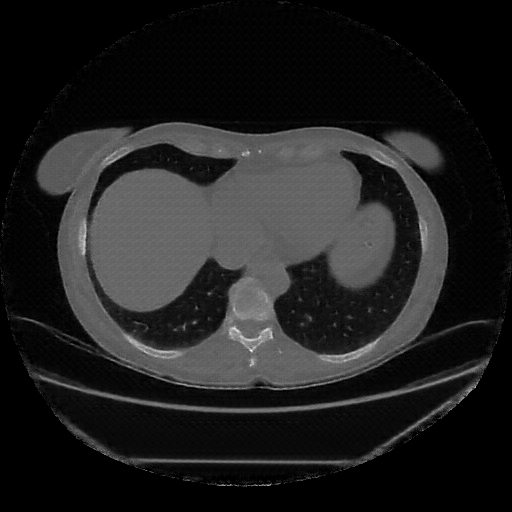

Image Grid

4Γ—3 grid: Rows show different image types (Original NATIVE, Reconstructed NATIVE, Original VENOUS, Generated VENOUS), Columns show windowing techniques (No Window, Lung Window, Mediastinum Window)

Reconstructed NATIVE CT scan (cycle consistency)

Full window (WL 1023.5, WW 4095 β†’ Low βˆ’1024, High +3071)

Lung window (WL -600, WW 1500 β†’ Low βˆ’1350, High +150)